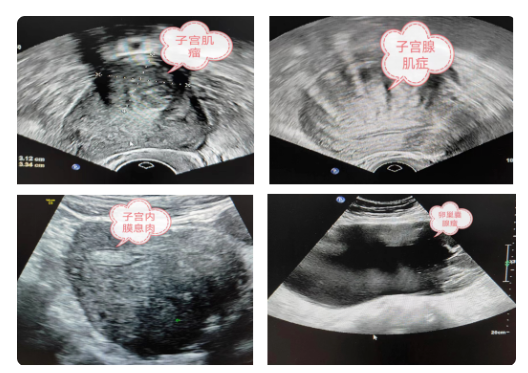

如上圖所示,盆腔彩超檢查的內(nèi)容是宮頸外口以內(nèi)的部分:包括子宮、卵巢、附件,常見的疾病如子宮肌瘤,子宮腺肌癥,子宮內(nèi)膜息肉,卵巢腫瘤,輸卵管積水、積膿、盆腔包塊等。(部分常見疾病超聲表現(xiàn)如下圖:)

image